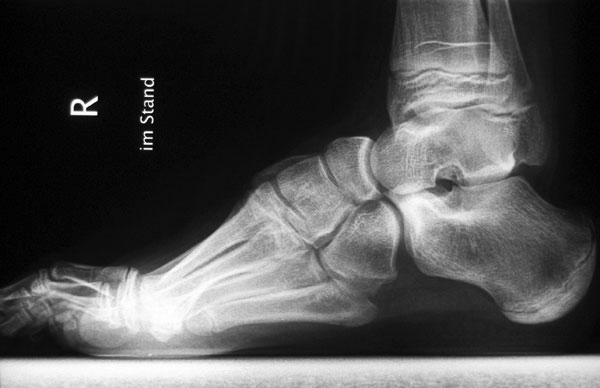

• Fuß belastet dp und seitlich (Abb. 14 und 15)

Typische Merkmale der Standard-Seitaufnahme des Fußes im Stand

• Knöchelgabel ist außen rotiert

• Talus und Calcaneus verlaufen fast parallel

• Sinus tarsi ist einsehbar

• Subtalare Gelenklinie verläuft horizontal und ist breit einsehbar

• Der Abstand Malleolus medialis zum Os naviculare ist verkürzt

• Der Calcaneus erscheint verkürzt

• Der Krümmungsscheitel des Fußes ist erhöht

• Calcaneus pitch ist meist erhöht, der Rückfuß Equinus ist eher selten 12